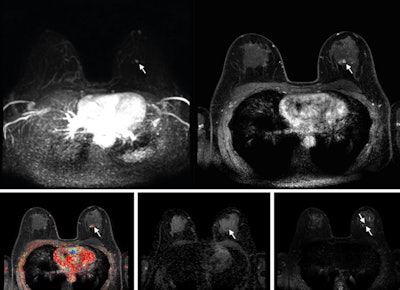

Abbreviated axial MRI images show a 7-mm irregular mass with irregular margin (arrows) in the right upper inner quadrant with early rapid enhancement (BIRADS 4). The participant was recalled and underwent an MRI-guided vacuum-assisted biopsy that showed sclerosing adenosis with microcalcifications and usual ductal hyperplasia and focal apocrine metaplasia. On the full-protocol images (not shown), the lesion was T2-weighted hypointense and showed diffusion restriction and washout kinetics in the delayed phase, characteristics that would not have reversed the decision to recall the participant.RSNA

Abbreviated axial MRI images show a 7-mm irregular mass with irregular margin (arrows) in the right upper inner quadrant with early rapid enhancement (BIRADS 4). The participant was recalled and underwent an MRI-guided vacuum-assisted biopsy that showed sclerosing adenosis with microcalcifications and usual ductal hyperplasia and focal apocrine metaplasia. On the full-protocol images (not shown), the lesion was T2-weighted hypointense and showed diffusion restriction and washout kinetics in the delayed phase, characteristics that would not have reversed the decision to recall the participant.RSNA